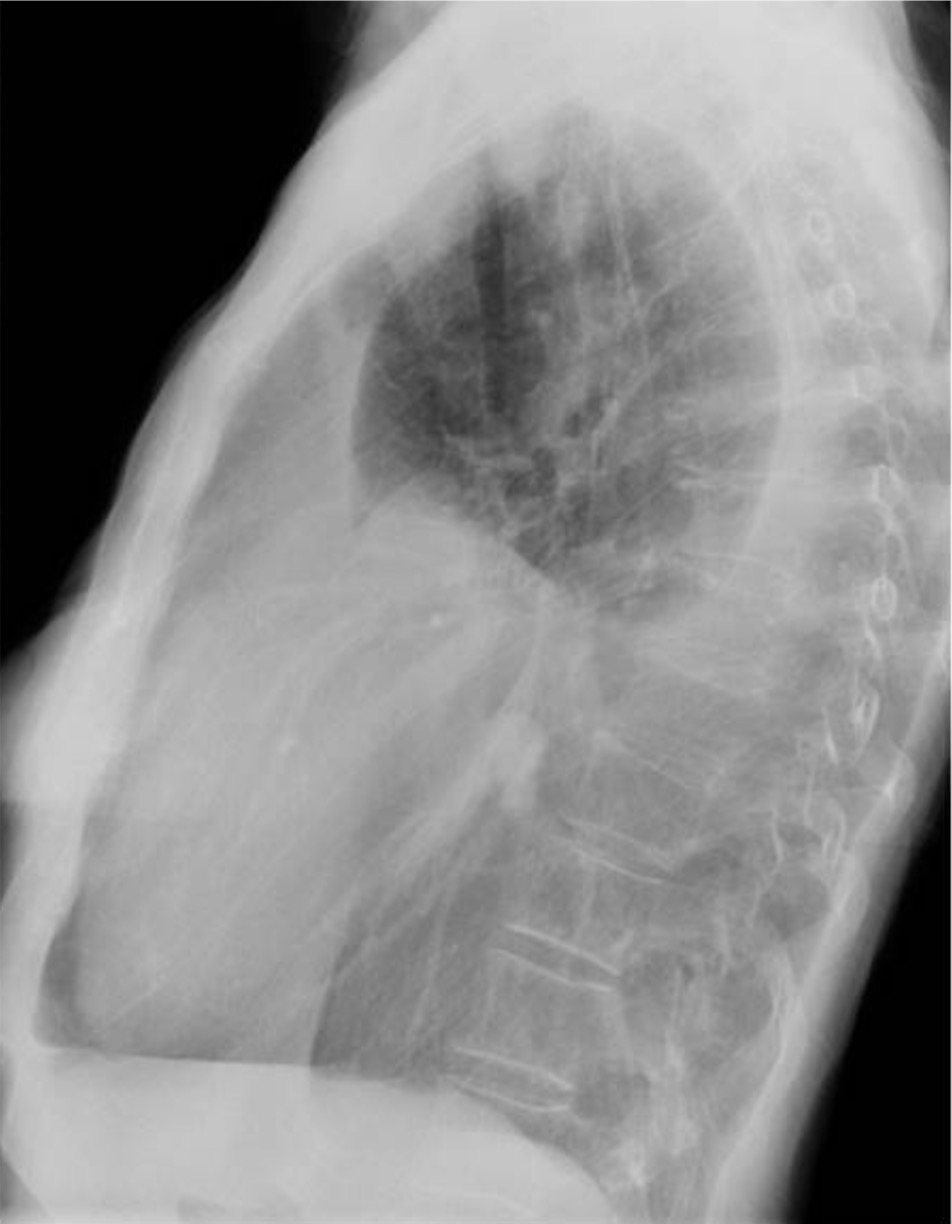

Rx lateral tórax

HALLAZGOS RADIOLÓGICOS

Opacidad homogénea bien delimitada en el hemitórax izquierdo sin desplazamiento mediastínico hacia la izquierda.

Opacidad homogénea mal delimitada en el hemitórax izquierdo sin desplazamiento mediastínico hacia la izquierda.

Opacidad homogénea bien delimitada en el hemitórax izquierdo con desplazamiento mediastínico hacia la izquierda.

Opacidad homogénea mal delimitada en el hemitórax izquierdo con desplazamiento mediastínico hacia la izquierda.